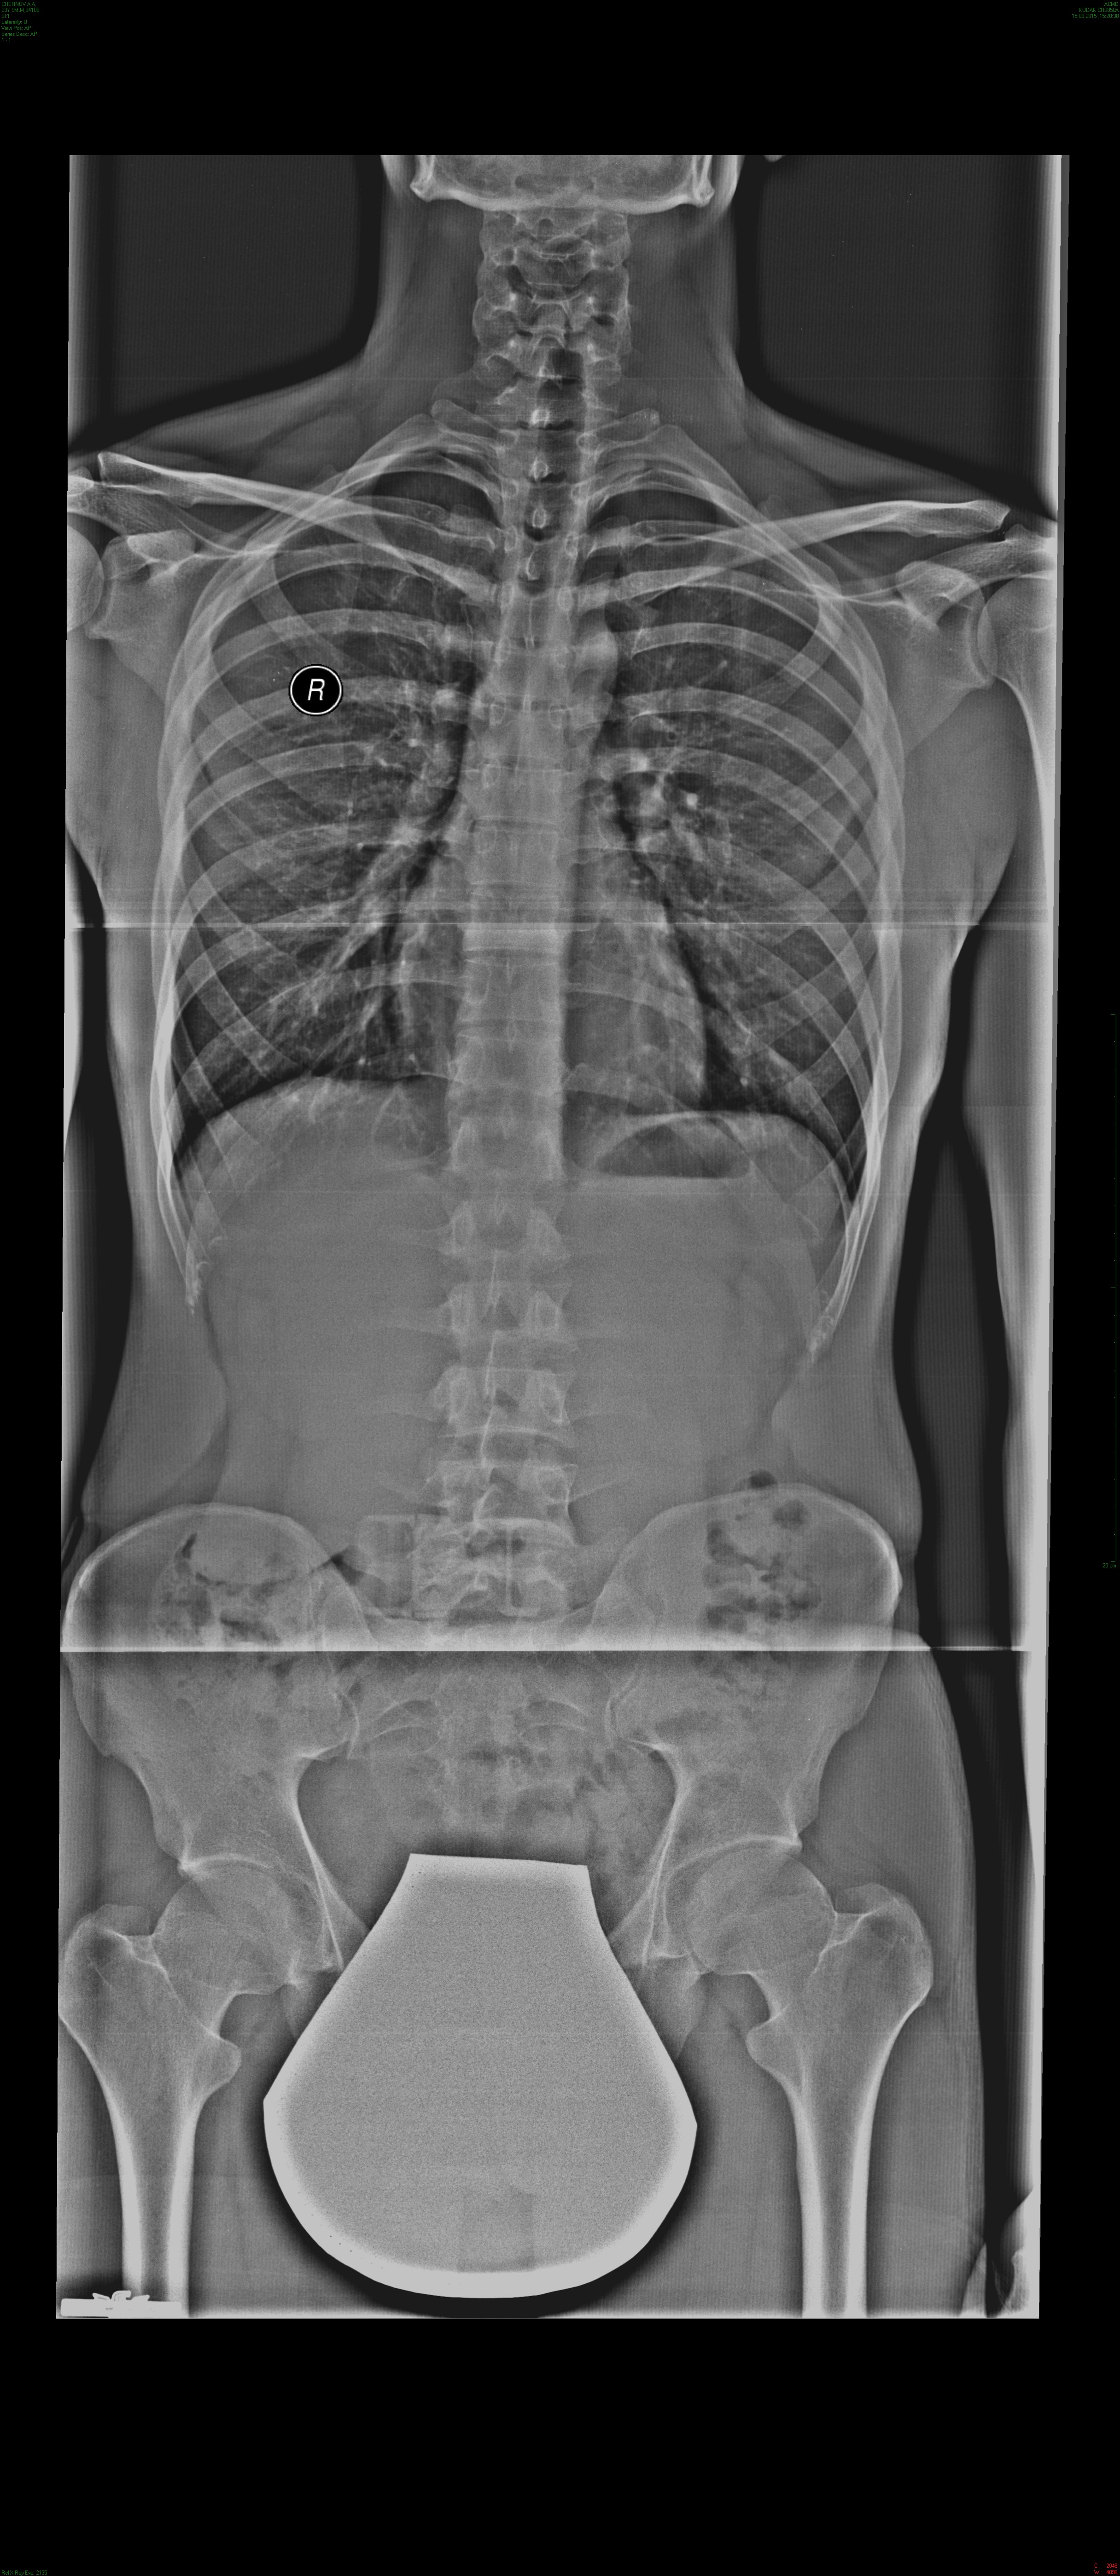

Добрый день. Мне 24 года. В 12 лет упал в яму. Приземлился вертикально, но сначала земли коснулась левая нога. В итоге треснула пятка, проносил гипс 2 недели. И еще порвалась губа в тазобедренном суставе и сместился таз но я тогда не обратил внимание. Вот спустя столько лет мне в феврале этого года сделали операцию на ТС. Удалили части порванной губы. Щас беспокоит перекос таза. Можно ли его выровнять в моем возрасте или он уже так сросся и нечего нельзя сделать? Беспокоит тем что тянет левую ногу вверх и она в итоге не дополучает нагрузку, то есть укороченная выходит из-за поднятого таза слева. В итоге боли а ТС и колене.